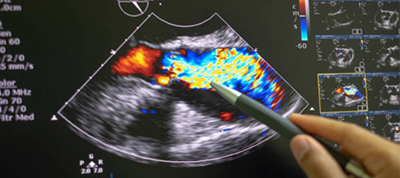

循環器科

循環器科とは、心臓と血管(動脈、静脈)に関する疾患の診察・治療を専門とする診療科です。主な疾患としては、心筋梗塞、狭心症、不整脈、心臓弁膜症、心筋症、心不全、先天性心疾患、大動脈瘤、閉塞性動脈硬化症、肺高血圧症、肺血栓塞栓症、高血圧、低血圧なとがあります。